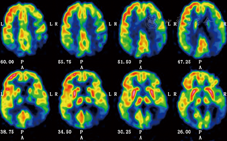

患者行18F-FDG PET检查,视觉分析显示该患者大脑皮质示踪剂呈不均匀分布,双侧颞顶枕联合区皮质、左尾状核和左额外侧皮质局灶性代谢减低(图2)。

PCA在已诊断痴呆的病例中占5%,在新诊断的痴呆病例中约占4%[5]。截至2010年,中国痴呆人数已逾千万,65岁人群痴呆发病率为9.87%[6]。由此推算,我国可能有超过500 000例的PCA患者,且该数量仍在快速增加,但国内有关PCA的神经影像学和神经病理学研究鲜有报道[7]。受限于我国国情,有关PCA的神经病理学研究开展相对困难,但随着18F-FDG PET和11C-PIB PET显像技术的不断发展,神经影像学对PCA的诊断作用日益凸显。本例患者头颅MRI提示顶枕叶萎缩明显,颞叶内侧萎缩不明显,这些表现有利于识别PCA并与典型阿尔茨海默病(Alzheimer′s disease,AD)相区别。但仅有头颅MRI证据是远远不够的,特别是疾病早期阶段,18F-FDG PET和11C-PIB PET通过显示脑代谢及β-淀粉样蛋白(Aβ)沉积,可为临床早期诊断PCA提供结构影像学之外的客观、独立证据[8]。FDG-PET功能成像研究提示PCA患者存在一致的顶枕区及后颞部皮质代谢减低[9]。Whitwell等[10]利用基于像素的形态测量学和质子磁共振波谱分析技术进行对照研究发现,PCA主要累及双侧枕叶、顶叶和颞叶后部,以右侧更明显。本例患者18F-FDG PET呈现较典型的右侧为著的颞顶枕联合区代谢减低,尤以右侧减低明显,与文献报道一致,提示PCA可能以右侧皮质变性为主。根据文献报道,PCA的病因包括AD、路易体痴呆、皮质下胶质细胞增多症、皮质基底节变性等,其中AD是最常见的病因。本例患者11C-PIB PET亦显示额颞顶枕皮质的Aβ沉积,与典型AD患者脑组织Aβ分布无明显差异,但关于PCA和AD患者老年斑和神经原纤维缠结分布的研究结果并不一致,有研究显示PCA和AD患者老年斑和神经原纤维缠结的分布不同[11],提示PCA可能为AD的一种特殊类型。